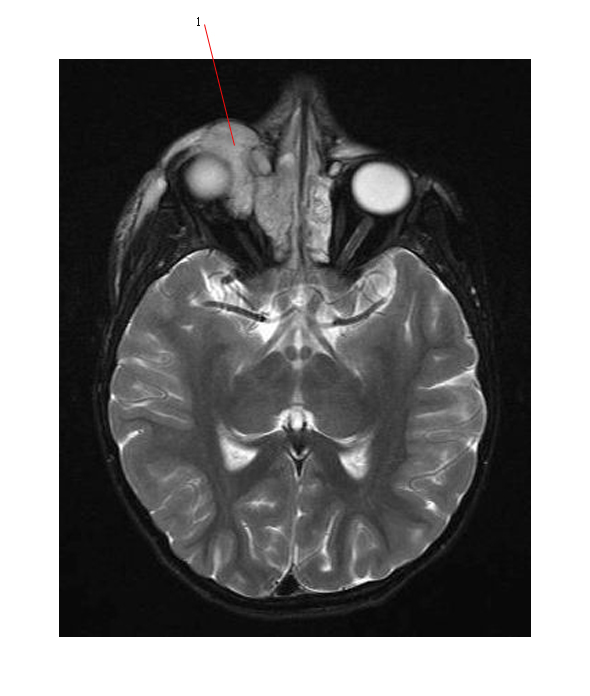

Rhabdomyosarcoma. EyeRounds.org - Ophthalmology - The University Of Iowa

webeye.ophth.uiowa.edu

webeye.ophth.uiowa.edu

rhabdomyosarcoma mri sphenoid ophth eyeforum webeye uiowa cases edu